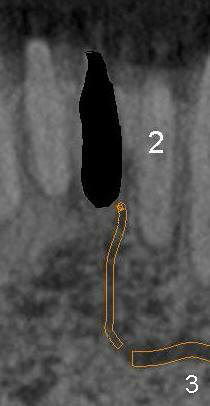

The incisive canal (Fig.1,2: I) is the anterior extension of the inferior alveolar canal (IA) after the latter gives rise to the mental nerve (circle). The terminal segment of the incisive canal (T or arrowheads in Fig.1) is located between the lower central (1) and lateral (2) incisors (3: lower canine).

After extraction of the central (Fig.3 black area), osteotomy for an immediate implant (Fig.4 white outline) should have a chance to violate the integrity of the terminal segment of the incisive canal, causing hemorrhage. Once the implant is placed, the hemorrhage should be able to stop.